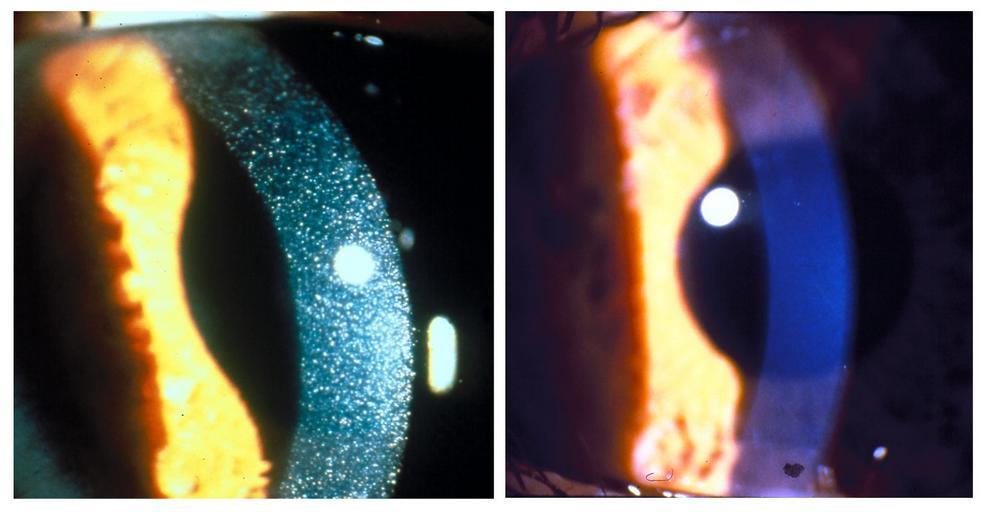

MAKE A MEME View Large Image Nephropathic cystenosis NHGRI-79209.jpg Slit-lamp photographs of three-year-old patient with nephropathic cystenosis before left and after right cysteamine eyedrop therapy Treatment targeting metabolic defect dramatically dissolves painful ...

Keywords: Nephropathic cystenosis NHGRI-79209.jpg Slit-lamp photographs of three-year-old patient with nephropathic cystenosis before left and after right cysteamine eyedrop therapy Treatment targeting metabolic defect dramatically dissolves painful crystals in the eye's cornea Avec une lampe à fente photo prise d'un patient de trois ans avec une cystinose néphropathique avant à gauche et après à droite une thérapie avec des gouttes de cystéamine Un traitement ciblant le défaut métabolique qui dissout de façon spectaculaire les cristaux douloureuses dans la cornée de l'oeil NHGRI genome gov http //www genome gov/dmd/img cfm node Photos/Technology/Medical Conditions id 79209 Date Taken 06/03/2010 Credit NIH Clinical Center Location National Institutes of Health Bethesda MD Slit lamp Cysteamine PD-USGov